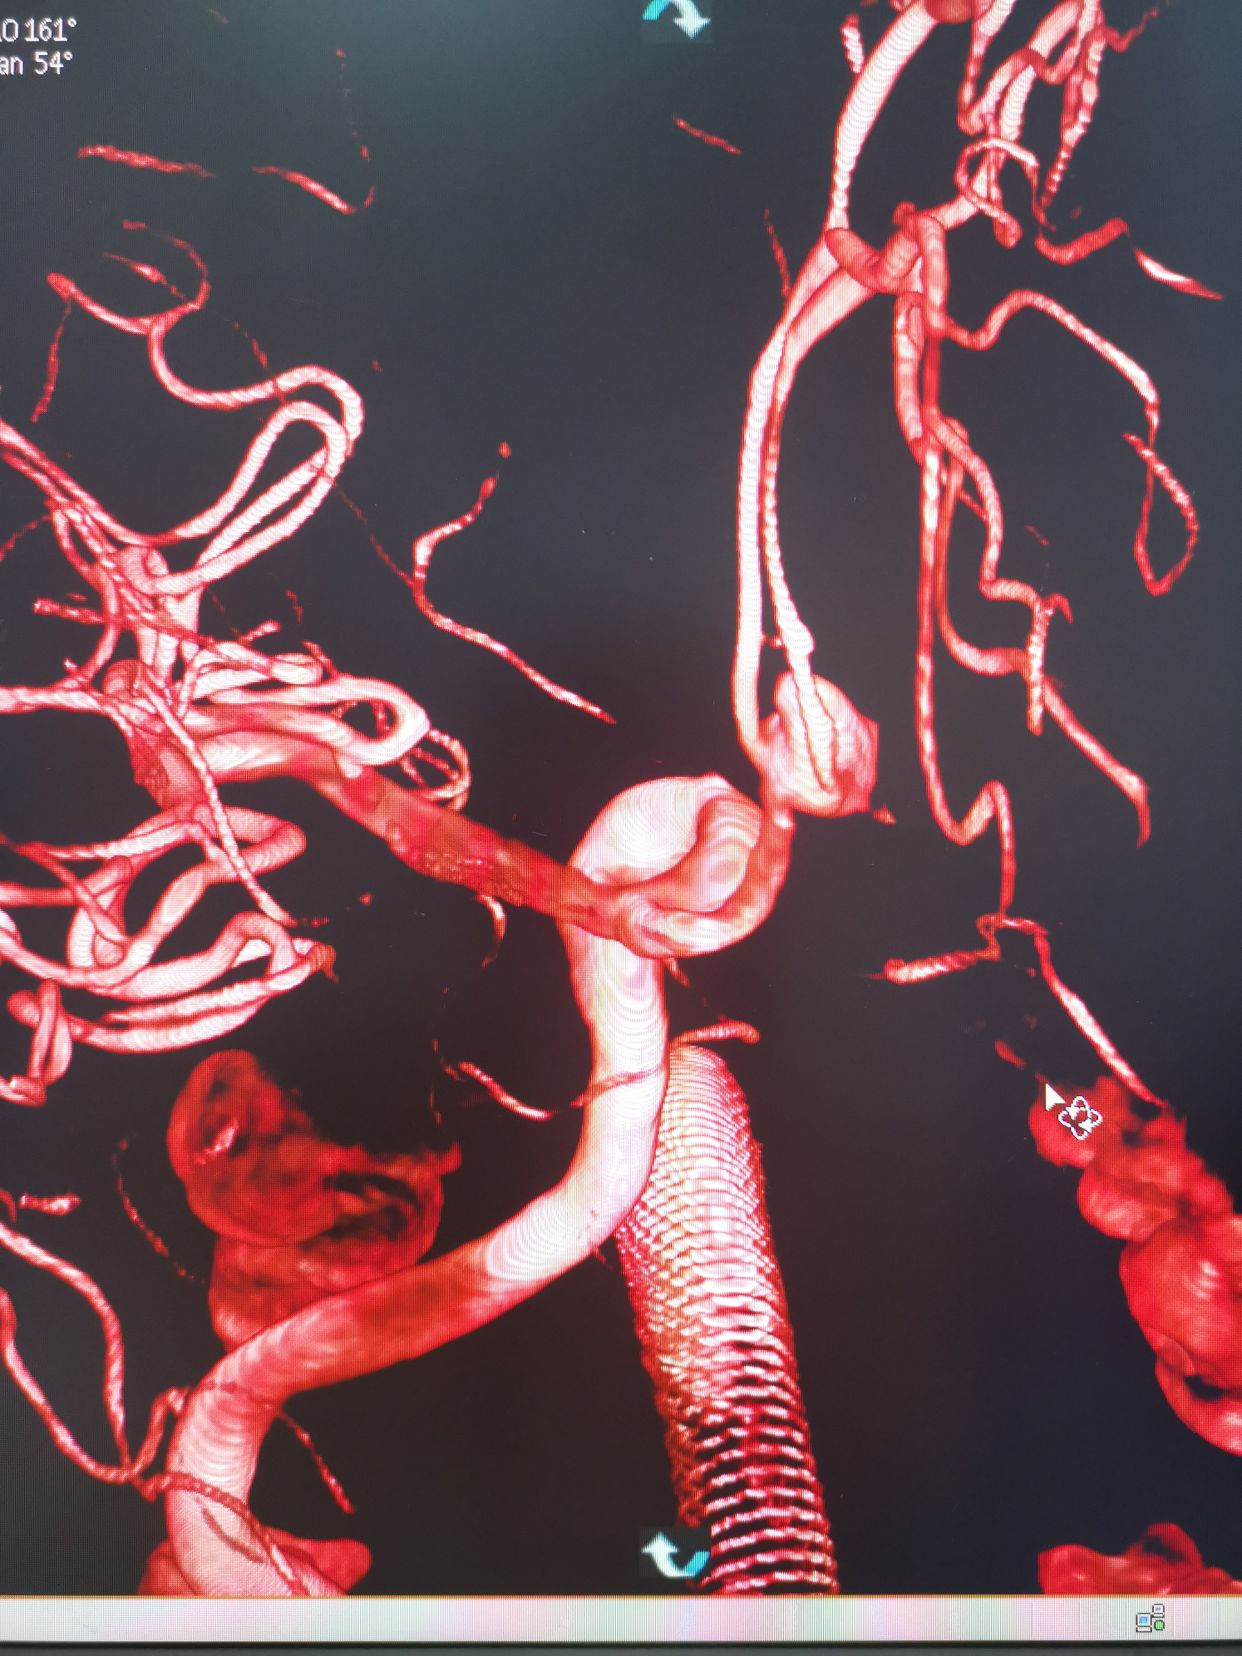

造影过程中,患者出现意识障碍加深,烦躁,不能配合,考虑颅内出的增加可能。术中请麻醉科老师急诊行气管插管麻醉。后行左侧颈内动脉3D造影。

左侧颈内动脉3D